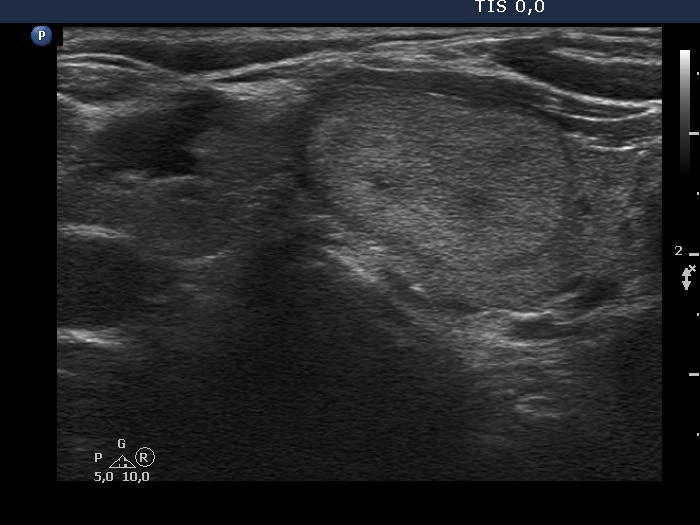

Ultrasonography. The thyroid was moderately hypoechogenic. There were several discrete lesions in the right lobe without any oncological significance. There was a hyperechoic nodule in the lower third of the left lobe, which corresponded to the positive focus on PET CT scan.